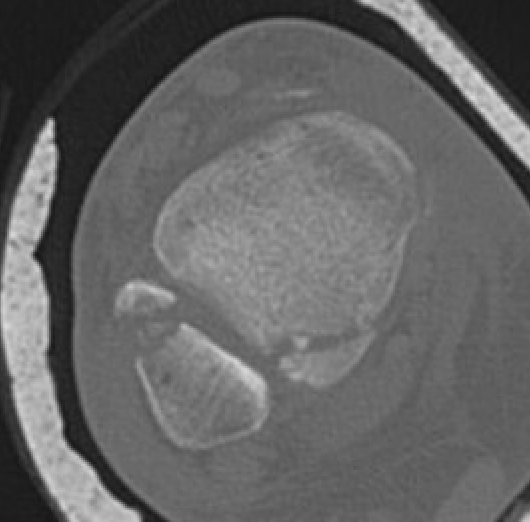

Mason and Malloy Classification

CT scan critical to classify and guide treatment / approach

| Type I | Type IIA | Type IIB | Type III |

|---|---|---|---|

| Avulsion of the PITFL |

Posterolateral fragment Volkmann fracture |

Posteromedial & posterolateral fragments Volkmann plus secondary fracture line |

Large coronal plane fragment Plafond fracture |